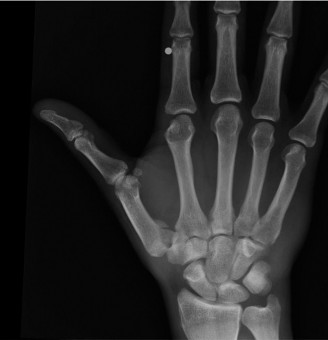

Identify complications of ORIF of hook and hamate fractures? Describe the anatomy of the hamate? CASE 17 A young sportsman presents with the following injury to his thumb ( Figure 3–14** ). What is your diagnosis?**

Figure 3–14(©) Sunil Thirkannad and Christine M. Kleinert.

The correct answer is (E). The lesion shown here is a Bennett’s fracture dislocation.